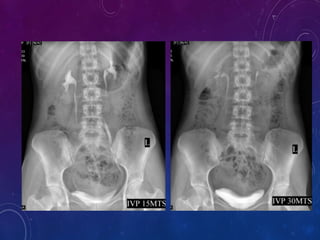

 If compression band is applied a film is taken after 10 minutes , the film

should shows centered kidneys to demonstrate distended collecting system

and proximal ureter.

15 minutes film :

1) Visualization of ureter is better in prone position as the fill better.

2) This position reverses curve of the inferior course of the ureters making it

anti-dependent is to gravity.

30 minute film:

1) It gives complete over view of the urinary tract ; Kidneys,Ureters,Bladder.

Bladder distension can be evaluated